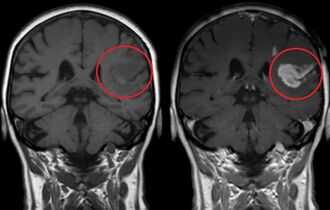

Доброкачественная опухоль на МРТ

Доброкачественные опухоли чаще всего характеризуются однородной структурой, из-за экспансивного роста имеют четкие, ровные контуры, вокруг таких новообразований отсутствует перифокальный отек. Кроме того, доброкачественные образования не накапливают или слабо накапливают контрастирующий препарат.